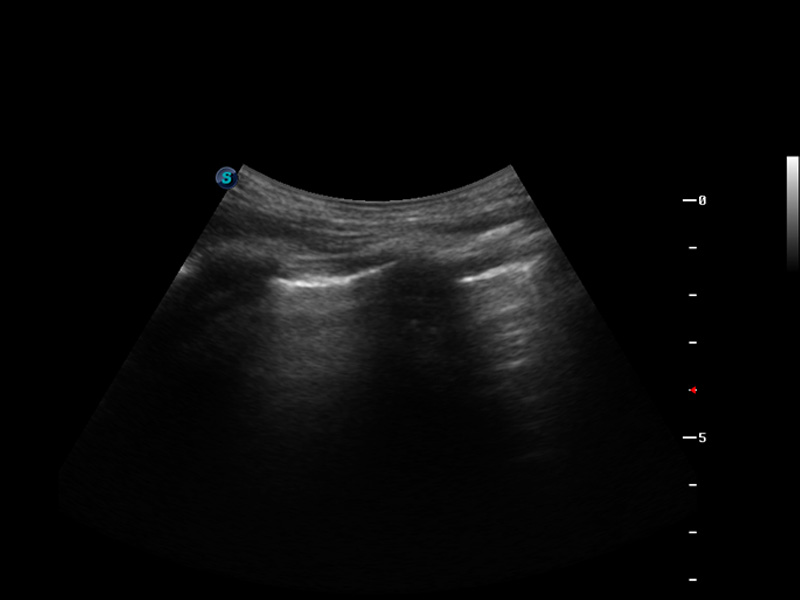

S9便携式彩色多普勒超声诊断仪是玖鼎集团研发的高端便携彩超设备,外观设计新颖、产品性能卓越。S9在便携超声领域采用了突破传统的触摸屏交互设计,并以先进的软件硬件技术和设计理念,为您带来清晰的图像质量、稳定的工作性能和便捷的操作体验。